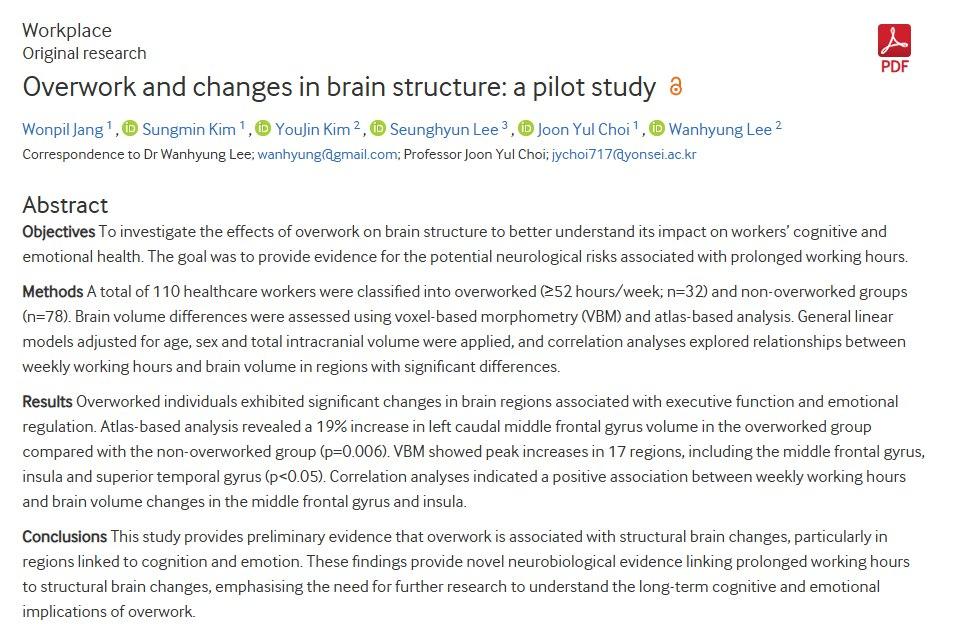

996伤脑?研究发现:长时间工作竟会改变大脑结构! 一项发表于《职业与环境医学》的研究一项最新研究显示,长时间工作可能导致大脑结构发生变化。研究人员对比了 overworked(每周工作≥52小时)和 non-overworked 两组医护人员的大脑结构,发现 overworked 组在与执行功能和情绪调节相关的大脑区域,如额中回、脑岛等,脑容量显著增加。 这表明,长时间工作可能引起大脑的适应性改变。 研究还发现,工作时长与这些脑区的容量变化存在正相关。 换句话说,工作时间越长,这些区域的脑容量增加越多。 这一结果为长时间工作对认知和情绪健康的潜在神经生物学影响提供了新的证据。 尽管研究人员认为这可能是大脑的一种适应性反应,但长期影响仍需进一步研究。 毕竟,大脑的改变是好是坏,现在下结论还为时过早。